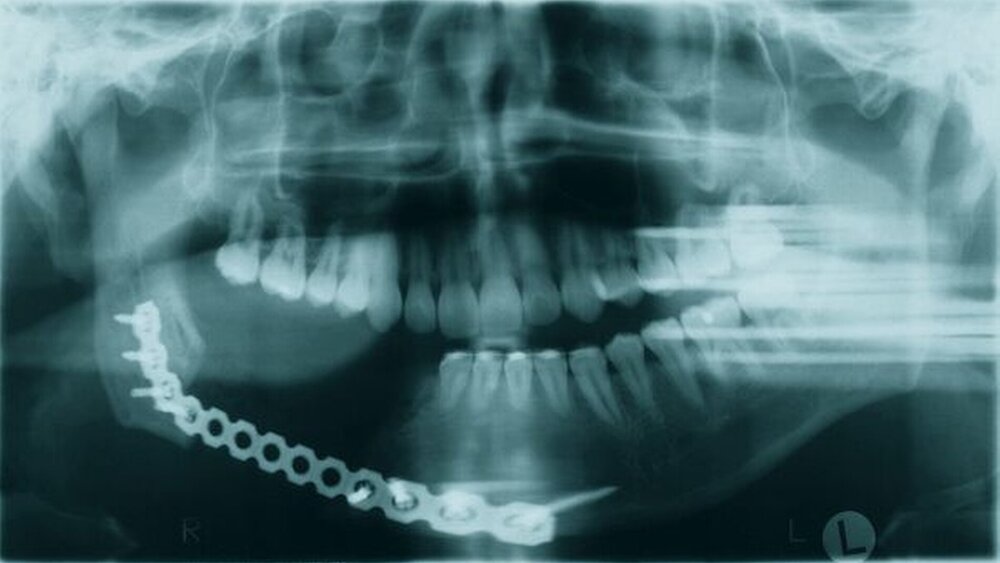

Auf der Basis der Diagnose eines malignen Tumors schloss sich nach abgeschlossenem Tumor-Staging (CT Kopf-Hals, PET, Rö-Thorax, Sono-Abdomen) die primäre Tumorresektion in Form einer Unterkieferkontinuitätsresektion (Abbildungen 4 und 5) sowie die supraomohyoidale Lymphknotenausräumung rechts an. Der entstandene Unterkieferdefekt wurde mit einer Titan-Rekonstruktionsplatte temporär überbrückt (Abbildung 6). Nach zwischenzeitlicher Nachresektion aufgrund eines tumorpositiven knöchernen Resektatrandes, wurde seitens der Pathologie die Entfernung des Tumors im Gesunden bestätigt und der Patient einer postoperativen Polychemotherapie entsprechend den Leitlinien für Osteosarkome zugeführt [www.awmf-leitlinien.de].